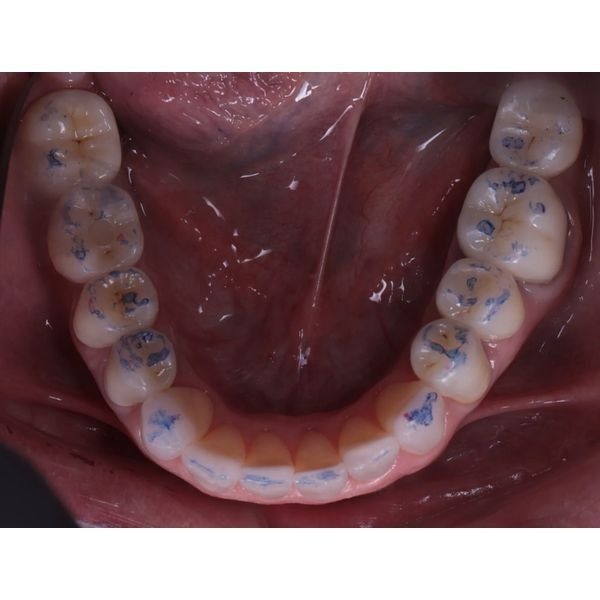

Жевательные поверхности боковых зубов оставались гладкими. Это говорило о том, что у пациентки не было окклюзионных помех, которые могли бы спровоцировать проблемы с височно-нижнечелюстным суставом (ВНЧС), однако из-за отсутствия рельефа контакт между зубами-антагонистами плоскостной, а не точечный, поэтому мышцам приходилось прилагать больше усилий, чтобы пережевать пищу.

В этом случае нам удалось добиться оптимального окклюзионного контакта. На динамических и статических пробах видно плотное, равномерное смыкание всех зубов. Это не только эстетически выигрышно, но и функционально: теперь жевание стало эффективнее, а нагрузка на суставы — физиологичнее.